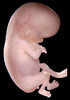

Carnegie Stage 23 (56 post-ovulatory days)

Most embryos at stage 23 are approximately 56-57 postovulatory days old and measure 23-32 mm in length. Distinguishing criteria for this stage include fusion of the eyelids at the medial and lateral margins, clear distinction of the subdivisions of the upper and lower limbs, the forearms appear at or above the level of the shoulders, the superficial vascular plexus of the head is very close to the vertex, and the external genitalia are well developed but not always sufficiently to distinguish the embryo's sex.

(NOTE: These specimens are late stage 23.)